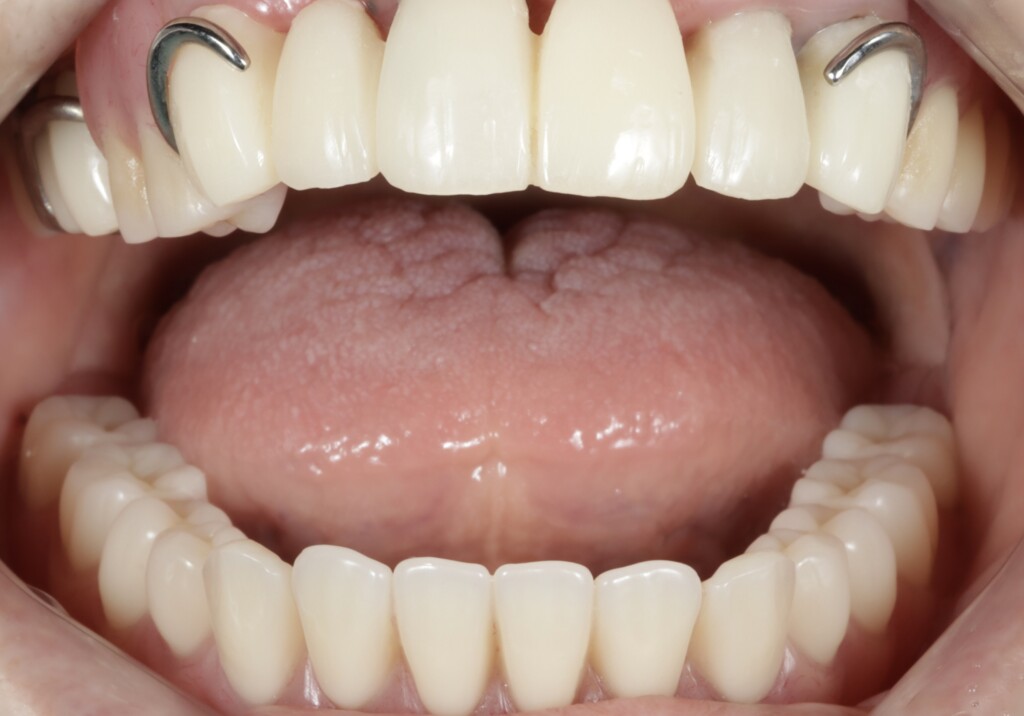

写真4:上顎の状態

上顎は、前歯部にブリッジ、右上奥歯には銀の被せ物が装着されている状態でした。しかし、それらを支えているご自身の歯との境目から虫歯が進行しており、残っている歯のほぼすべてに問題が認められました。特に右上の前歯は、歯ぐきの下にまで虫歯が進行しており、汚れが溜まりやすい状態となっていたため、歯ぐきにも強い炎症がみられました。また、その他の歯についても、虫歯ではない健全な歯質が歯ぐきの縁付近までしか残っていない状態で、歯としての支える力が大きく低下していました。

上顎の残っている歯は、これまでブリッジや被せもので連結されていたため分かりにくい状態でしたが、詳しく評価を行ったところ、左上の犬歯(糸切り歯)を除き、いずれの歯にも動揺が認められました。また、骨に埋まっている部分(支持組織)も少なく、歯を支える力が低下している状態でした。この点については、治療開始前の検査の段階である程度予測はできていましたが、実際には歯ぐきより上に十分な健全歯質も残っていない状況でした。このような歯に対して、ブリッジやクラウンのように歯へ大きな負担がかかる治療方法を選択し、さらに部分入れ歯の留め金をかける設計とした場合、負担が集中し、状態の悪化を招く可能性があります。そのため今回は、支える力が低下している歯への負担をできる限り抑える設計として、磁性アタッチメントを用いた入れ歯をご提案しました。